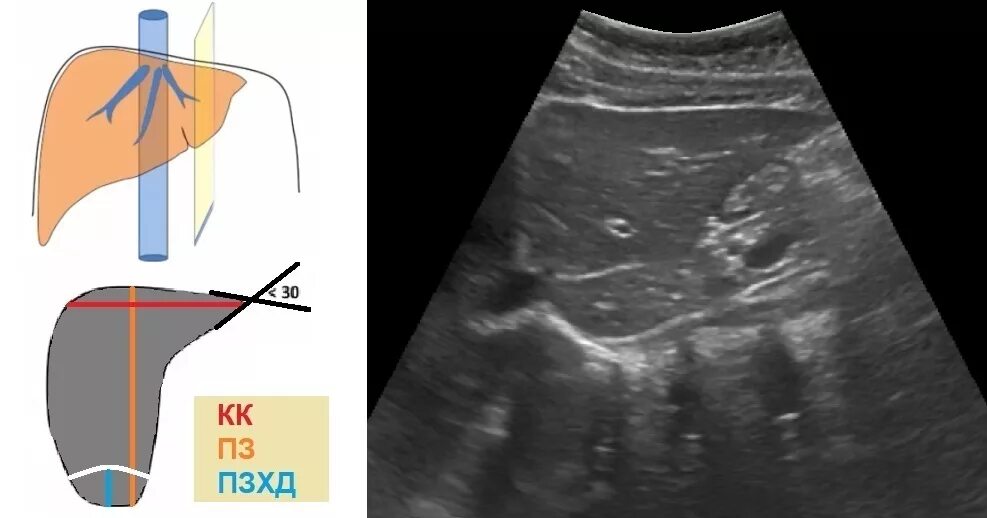

Подготовка к узи печени у взрослых